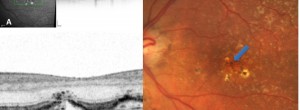

Direct Visualization of a New Choroidal Vessel on Spectral-Domain Optical Coherence Tomography

Correspondence. Wedge-Shaped Subretinal hyporeflectivity in GA.